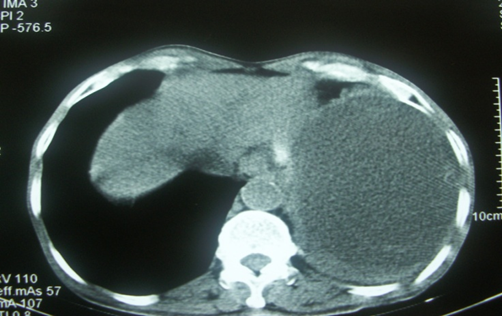

3. Hematoma intraabdominal localizados, sin compromiso hemodinámico

Ilustración 5 Tomografía abdominal con Hematoma esplénico localizado sin compromiso hemodinámico

Fuente: Hospital de Especialidades Guayaquil “Doctor Abel Gilbert Pontón”.

Autor: Dr. Fernando Moncayo A.